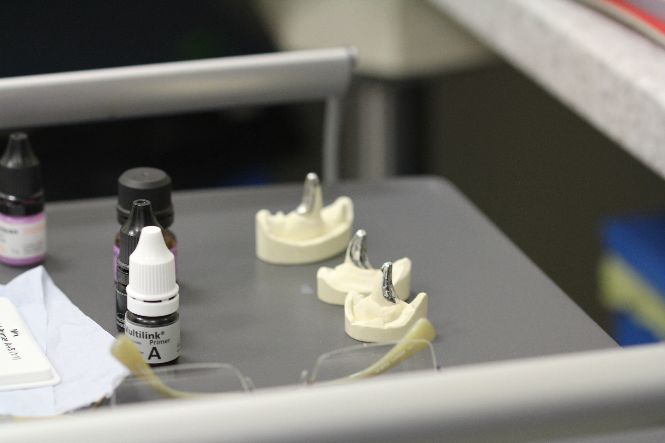

The impressions were sent to a dental lab called Dental Precision in Cornwall where the crowns were made. They are three quarter cast metal crowns. The crowns cover, protect and strengthen the damaged surfaces of the canine teeth, preventing further tooth damage and tooth fracture.

Completed crowns ready for cementation